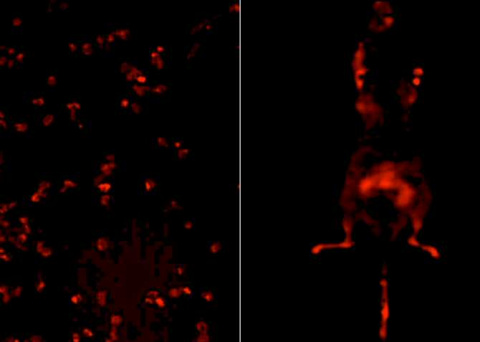

"La sobreexpresión de hnRNP K suele estar asociada con una baja tasa de recuperación de la enfermedad y supervivencia", explica Gallardo. "Esto se ha confirmado con estudios que revelan que la sobreexpresión del hnRNP K en ratones transgénicos conduce al desarrollo de linfomas y a una reducción de la supervivencia".